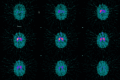

Patients with chronic liver disease (CLD) are prone to complications associated with impaired liver functioning. This coupled with iron-deficiency anaemia (IDA) can predispose them to multiple comorbidities. We present an interesting case of a 69-year-old woman with a background history of liver cirrhosis due to metabolic dysfunction-associated steatotic liver disease (MASLD) with frequent travels to Bangladesh, a southeast Asian country known for having high levels of manganese (Mn) in water for domestic use. She presented with progressively worsening cognition and extrapyramidal symptoms. She underwent routine blood tests including for liver functions followed by a non-contrast computed tomogram (CT) of the head that did not suggest a possible cause. However, magnetic resonance imaging (MRI) of the brain showed hyperintensities bilaterally in the globus pallidus, subthalamic nucleus, red nucleus, and substantia nigra and raised the possibility of Mn toxicity. This was confirmed with repeated raised blood levels of Mn. The query was raised for acute toxicity to Mn, followed by consideration of CLD history associated with reduced elimination of Mn. This was complicated further by her history of IDA. Her case was discussed in a multi-disciplinary setting with specialities including radiology, gastroenterology, neurology, psychiatry, hepatology, and elderly medicine. Following this, a decision was made for the best supportive management of the patient. This case highlights the importance of MRI in the detection of a rare case of Mn toxicity, in a predisposed individual contributing to cognitive decline with extrapyramidal symptoms.